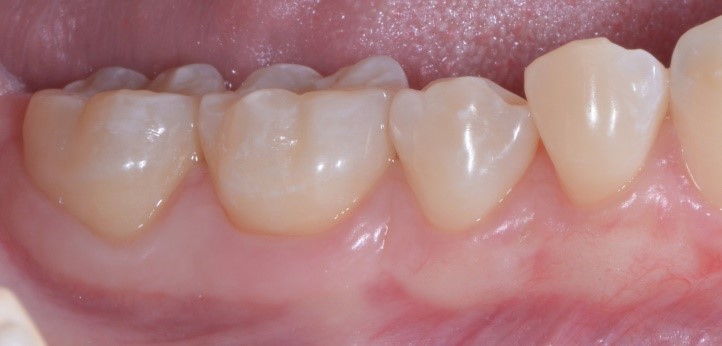

Cosa vedi di strano nella foto qui sotto? Ti sembra che la gengiva di Francesca abbia dei problemi?

gestione dei tessuti molli - aspetto dei tessuti molli

Io direi proprio di no e sicuramente tu non puoi che concordare con me. Una bella gengiva rosa e sana.